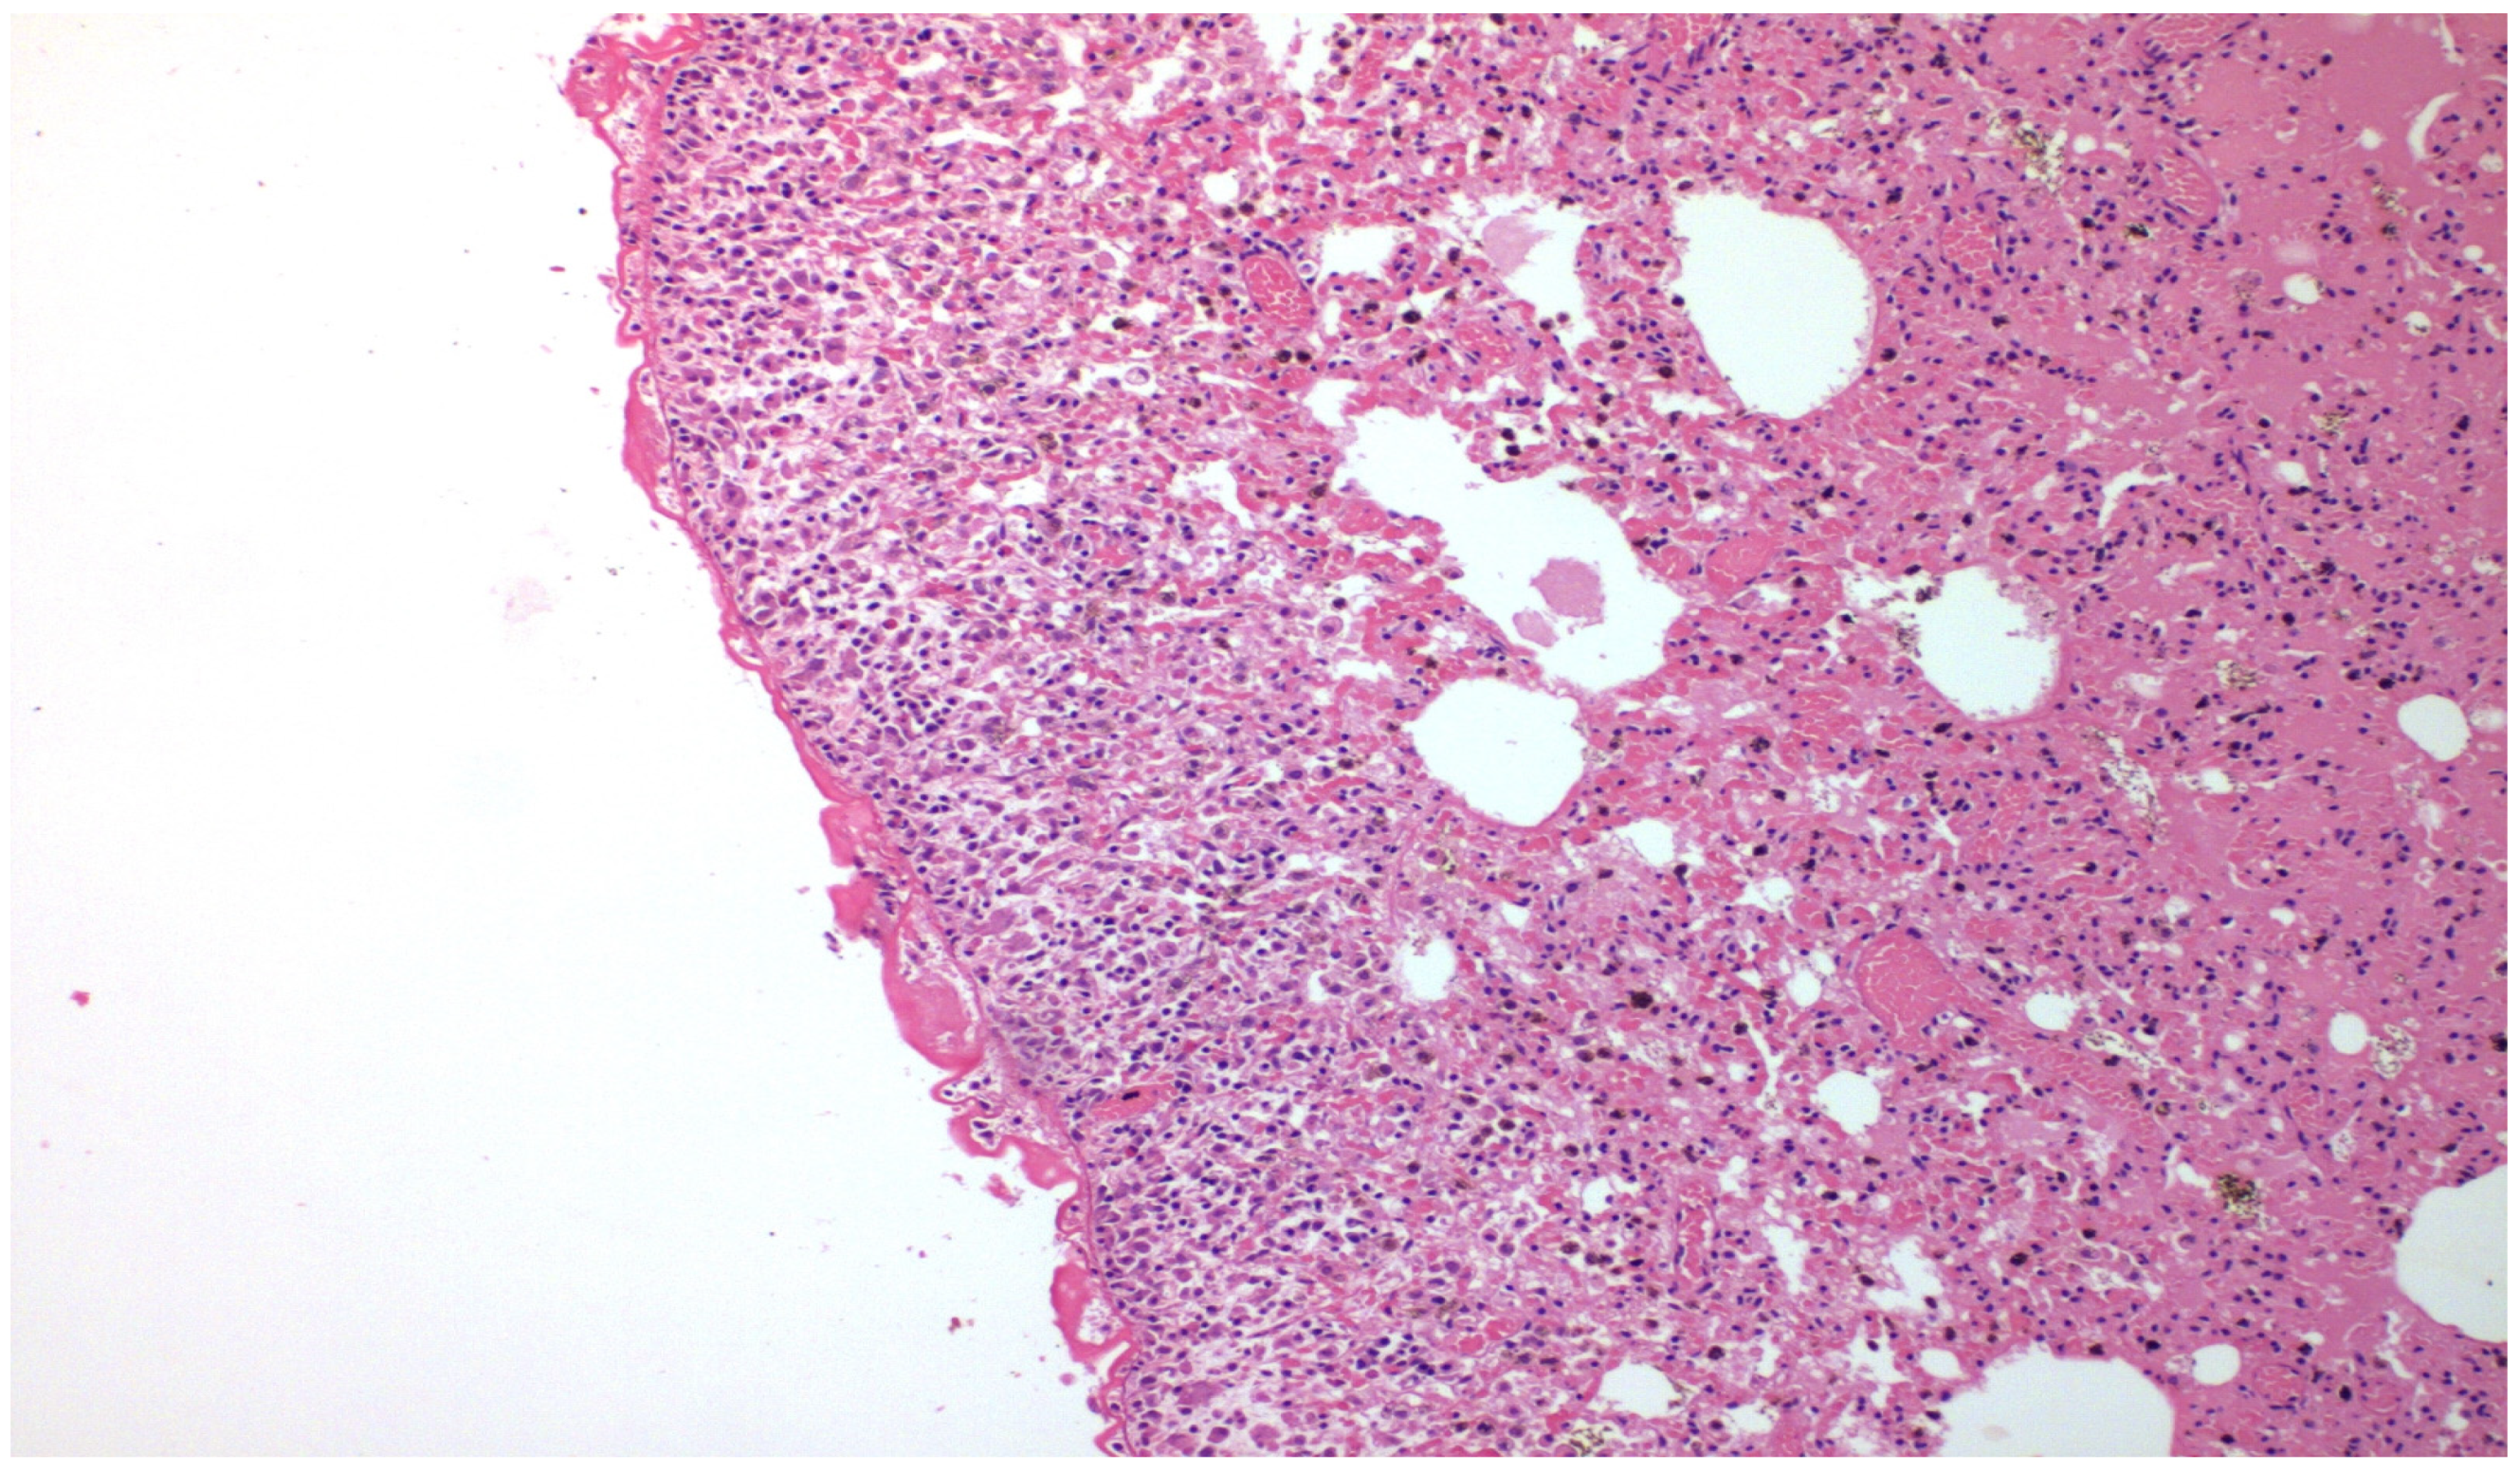

- With talc, there was a statistically significant difference in the inflammation provoked in 6 days compared to 3 days regarding parietal pleura (p = 0.002) (Figure 11); regarding visceral pleura, this could not be measured, as inflammation was high in both groups (grade II–III).